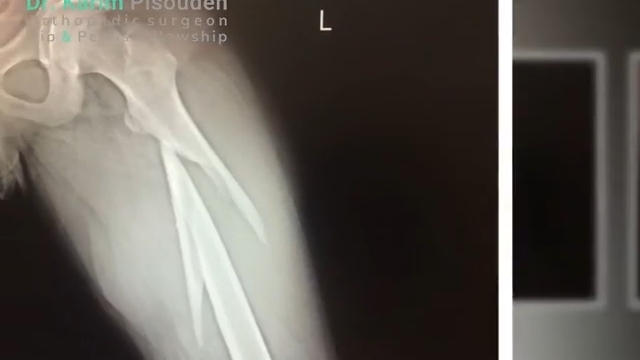

شکستگی ناحیه ساب تروک بر اثر تصادف

دکتر کریم پیسوده متخصص ارتوپد و فلوشیپ هیپ و لگن